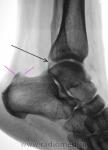

1. Не ясно, что здесь ( черная стрелка).

2. Я бы сделал пяточную кость во второй проекции.

на консолидированный перелом Фолькмановского клина б\берцовой кости.

А, может быть, с учетом деформации малоберцовой кости, на боковой рентгенограмме, можно предположить, что, "это", откол фрагмента костной ткани от дистального эпифиза б/берцовой кости.